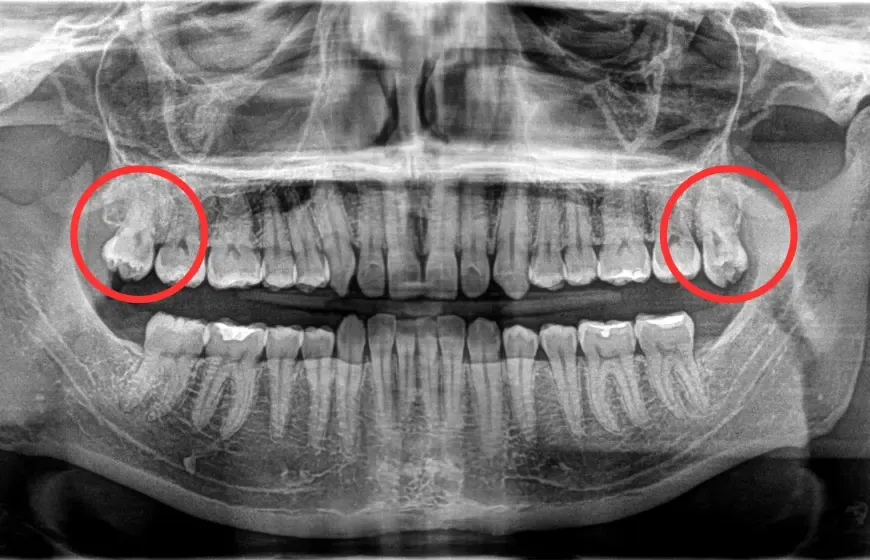

- Nie każdy ma zawiązki wszystkich zębów mądrości to cecha ewolucyjna, a ich obecność sprawdza się zdjęciem pantomograficznym.

Jednym z najczęstszych problemów jest tzw. ząb zatrzymany. Oznacza to, że ząb mądrości jest w pełni uformowany, ale nie może się przebić przez dziąsło i pozostał całkowicie w kości szczęki lub żuchwy. Taki ząb, choć niewidoczny, może stanowić poważne zagrożenie. Brak możliwości wyrznięcia się może prowadzić do rozwoju stanów zapalnych, bólu, a nawet uszkodzenia sąsiednich struktur kostnych i korzeni innych zębów.

Współczesne szczęki często są mniejsze niż te, które były potrzebne naszym przodkom. W rezultacie, brakuje miejsca na prawidłowe wyrznięcie się wszystkich ósemek. Gdy ząb próbuje się wyrzynać w ciasnocie, może przyjąć nieprawidłowy kierunek wzrostu. Wówczas zaczyna naciskać na korzenie sąsiednich zębów, najczęściej siódemek. Ten nacisk może prowadzić do ich uszkodzenia, resorpcji korzeni, a także powodować stłoczenie pozostałych zębów, wpływając negatywnie na zgryz.

Niewyrznięte zęby mądrości, zwłaszcza te zatrzymane, mogą prowadzić do rozwoju poważniejszych powikłań. Jednym z nich jest powstanie torbieli. Torbiel to jama wypełniona płynem, która rozwija się wokół zatrzymanego zęba. Z czasem może ona powiększać swoją objętość, niszcząc otaczającą kość szczęki lub żuchwy oraz korzenie sąsiednich zębów. Dodatkowo, trudności w utrzymaniu higieny wokół ósemek znacząco zwiększają ryzyko rozwoju próchnicy, zarówno na samym zębie mądrości, jak i na sąsiednich zębach. Regularne kontrole stomatologiczne pozwalają na wczesne wykrycie tych zagrożeń.